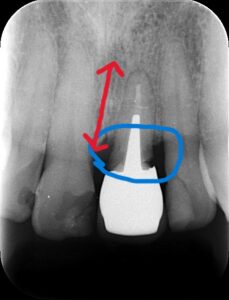

レントゲンでは青色の部分が虫歯に感染しており

赤色が根の長さのため十分な長さがとれず抜歯と

計画致しました。